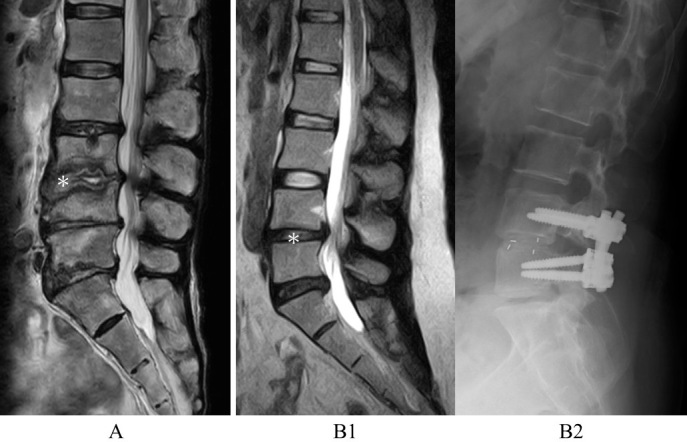

Methods: A total of 85 patients with lumbar pyogenic spondylitis (the infected group) and 156 with lumbar spondylosis who underwent posterior lumbar interbody fusion (the noninfected group) were retrospectively evaluated. Patients with a previous history of spinal fusion, tuberculous spondylitis, and multilevel infection and those receiving dialysis were excluded. Magnetic resonance imaging of the lumbar spine was conducted. Each disc at the L1/2-L5/S levels was graded. The total score of the four discs, excluding the affected disc, was used as the modified disc degenerative disease (DDD) score. Propensity score matching was performed using independent variables such as age, sex, diabetes mellitus, cancer, and steroid use. The modified DDD scores at all and each disc level were compared between the two matched groups.

Results: After matching, 48 patients in the infected group and 88 in the noninfected group were finally included in the study. The mean modified DDD scores of the infected and noninfected groups were 7.63 and 5.40, respectively. The modified DDD scores at all and each disc level were higher in the infected group than in the noninfected group.